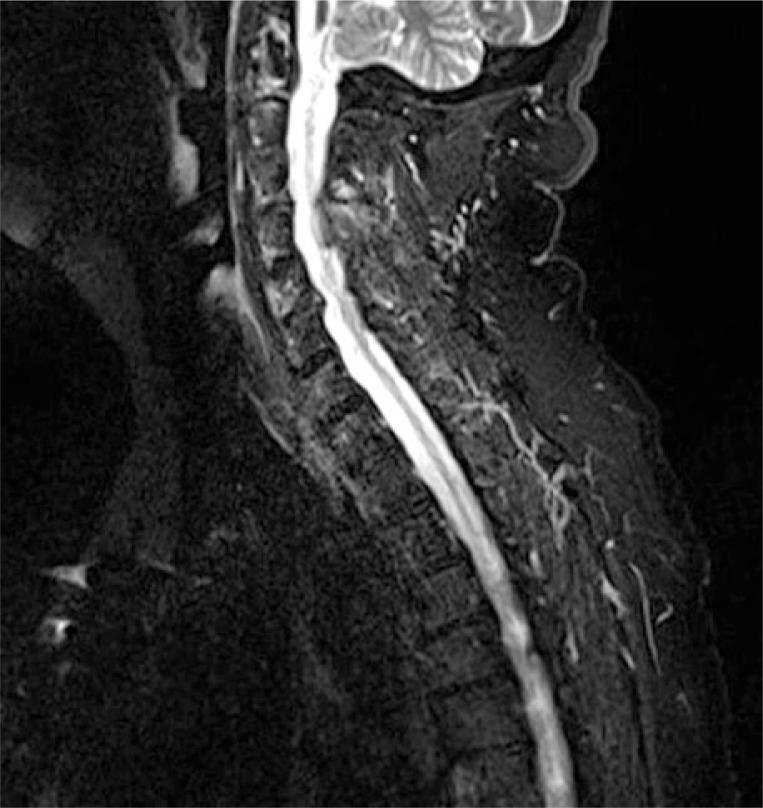

Among the rheumatic diseases whose symptoms are more often associated with the possibility of cancer and other malignancies are systemic sclerosis, dermatomyositis and rheumatic polymyalgia. However, a differential diagnosis should be performed in each case of non-typical rheumatic disease and/or other neoplastic disease risk factors. The article's aim was based on a literature review of this subject and presentation own a case description and discussion about arthritis as a paraneoplastic syndrome. The conclusions of our analysis were as follows: more often paraneoplastic arthritis occurs in men, in ages higher than 50 years old, in patients who poorly respond to treatment of arthritis with polyarticular symmetrical involvement of the limbs, seronegative type of inflammatory joint disease. In this group of patients, complete remission after treatment of the primary tumor and recurrence of the symptoms in the presence of metastasis was observed.

在症状更常与癌症及其他恶性肿瘤可能性相关的风湿性疾病中,有系统性硬化症、皮肌炎和风湿性多肌痛。然而,对于每一例非典型风湿性疾病和/或其他肿瘤性疾病风险因素的病例,都应进行鉴别诊断。本文的目的基于对该主题的文献综述,并呈现了一个关于关节炎作为副肿瘤综合征的病例描述及讨论。我们的分析结论如下:副肿瘤性关节炎更常发生于男性、50岁以上人群、对四肢多关节对称性受累的关节炎治疗反应不佳的患者、血清阴性类型的炎性关节病患者。在这组患者中,观察到原发性肿瘤治疗后完全缓解以及出现转移时症状复发的情况。